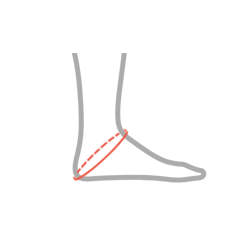

| Rozmiar | Obwód przez piętę | Sposób dokonywania pomiaru |

| Uniwersalny | min 26 cm – max 40 cm |  |

Wyrób uniwersalny na prawą i lewą nogę.

Całkowita wysokość ortezy: 25 cm